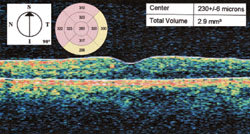

Figure 2. OCT before the subthreshold micropulse diode laser treatment showing mild retinal thickening in the perifoveal and foveal areas. |

The fluorescein angiogram demonstrated a normal FAZ with leaking microaneurysms in the parafoveal area (Figure 1). Optical coherence tomography (OCT) (Stratus OCT,

Carl Zeiss Meditec, Dublin, Calif) revealed minimal thickening within the 3.45-mm diameter area centered at the foveola (Figure 2). Subthreshold micropulse diode laser photocoagulation was recommended due to the proximity of the retinal edema to the fovea in a patient with an ETDRS VA of 20/20.

Figure 4. OCT after 2 subthreshold micropulse diode laser treatments (8 months after the first treatment). The central foveal thickness has decreased from 230 μm to 207 μm. The perifoveal thickness within the 3.45 mm radius (within the 2 rings around the fovea) has also decreased when compared to the prelaser OCT (Figure 2). |